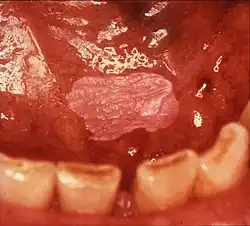

Erythroleukoplakia (also termed speckled leukoplakia, erythroleukoplasia or leukoerythroplasia) is a non-homogeneous lesion of mixed white (keratotic) and red (atrophic) color. Erythroplakia (erythroplasia) is an entirely red patch that cannot be attributed to any other cause. Erythroleukoplakia can therefore be considered a variant of either leukoplakia or erythroplakia since its appearance is midway between.[22] Erythroleukoplakia frequently occurs on the buccal mucosa in the commissural area (just inside the cheek at the corners of the mouth) as a mixed lesion of white nodular patches on an erythematous background,[22] although any part of the mouth may be affected. Erythroleukoplakia and erythroplakia have a higher risk of cancerous changes than homogeneous leukoplakia.[22]

- Red lesions (erythroplasia) and mixed red and white lesions (erythroleukoplakia/"speckled leukoplakia") have a higher risk of malignant change than homogeneous leukoplakia.[15]